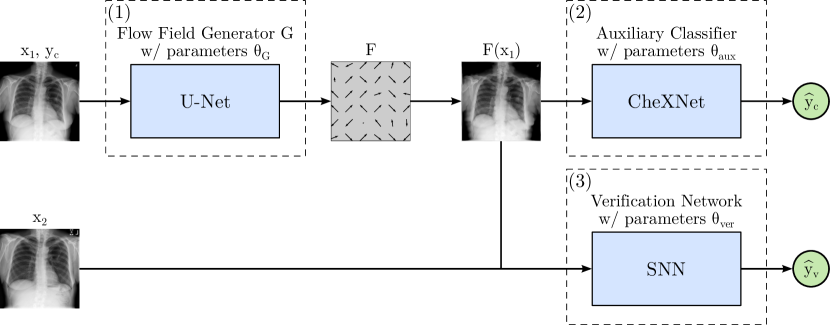

Refer to caption

Figure 1: PriCheXy-Net: Proposed adversarial image anonymization architecture.

The proposed adversarial image anonymization approach is depicted in Fig. 1. It is composed of three trainable components: (1) A U-Net generator G𝐺G that predicts a flow field F𝐹F used to deform the original image x1subscript𝑥1x_{1} of abnormality class ycsubscript𝑦𝑐y_{c}, (2) an auxiliary classifier that takes the modified image F(x1)𝐹subscript𝑥1F(x_{1}) resulting in corresponding class predictions y^csubscript^𝑦𝑐\hat{y}_{c}, and (3) a siamese neural network (SNN) that receives the deformed image F(x1)𝐹subscript𝑥1F(x_{1}) as well as another real image x2subscript𝑥2x_{2} of either the same or a different patient and yields the similarity score y^vsubscript^𝑦𝑣\hat{y}_{v} for patient verification. The U-Net serves as an anonymization tool aiming to obfuscate biometric information through targeted image deformations, while the auxiliary classifier and the patient verification model contribute as guidance to optimize the flow field generator.